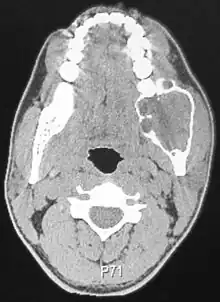

Diagnosis

Ameloblastoma is tentatively diagnosed through radiographic examination and must be confirmed by histological examination through biopsy.[8]

Radiographically, the tumour area appears as a rounded and well-defined lucency in the bone with varying size and features. Numerous cyst-like radiolucent areas can be seen in larger tumours (multi-locular) giving a characteristic "soap bubble" appearance. A single radiolucent area can be seen in smaller tumours (unilocular).[8] The radiodensity of an ameloblastoma is about 30 Hounsfield units, which is about the same as keratocystic odontogenic tumours. However, ameloblastomas show more bone expansion and seldom show high density areas.[14]

Lingual plate expansion is helpful in diagnosing ameloblastoma as cysts rarely do this. Resorption of roots of involved teeth can be seen in some cases, but is not unique to ameloblastoma.[10]